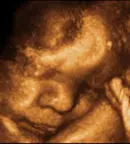

Hello Dr. Bencic, This is Pavel Dichkovski. I and my wife, Valeryia Bakunovich, visited you yesterday (30/4) on emergency after a car accident that we experienced. I have a question regarding the medicine you prescribed - Apaurin. Valeryia took two tablets (one yesterday, one today) and has experienced strong effects of the tablets (weakness, slowness, narkotic effects). We immediately stopped and read the instructions of Apurin. To my dismay, I discovered that this medicine is not allowed in the first three-mestr of pregnancy due to its pervasiveness through placenta and negative effects on breathing and blood circulation of the baby! I have two questions with this regard: - Are you aware of these side effects of Apaurin? - And if Yes - why did you prescribed it to my wife knowing that she's on the 9th week of pregnancy?! Please let me know as urgent as possible. Best regards, Pavel Dichkovski

Hello Mr.Dichkovski, sorry for late response - I was travelling without my laptop. I know perfectly about farmaceutical prescribes of diazepam (Apaurin, Valium, Normabel) and inspite of this I prescribe Apaurin 2 mg tbl 1-2 time daily in early pregnancy like usual in great clinics all over the world. Don't worry, experience during more than 40 years tell us that this therapy gives very important benefit and only minimal theoretical risk in early pregnancy. In medicin sometimes doktor must choise among great benefit and low risk. You must know that today all farmaceutic.industry use to scribe all theoretically possible complications of -any medicine so that they are perfectly protect in case of some juridic problem. So very often the patient , reeding prescribes, stop with therapy and this is not allways good, is better talk with doktor who knows practise. If your wife was very sleepy was enough to reduse therapy on 1 tbl Apaurin 2 mg in the evening. Any way, don't worry, for baby wasn't any risk. Taking Apaurin 5-10 mg tbl 2-3 time daily is one other story - is dangerous for baby. I hope that now is all in order with your wife end baby. And I hope too that you understand that I wish all the best for my patients and after 45 years of experience I know what to do. Best regards, Dr.Dunja Benčić